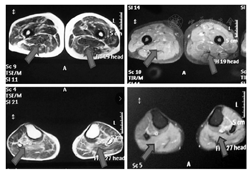

血常规、风湿三项、叶酸、维生素B12水平、血沉、电解质、空腹血糖均正常;肾功能检查,尿酸测定494 μmol/L;肝功功能检查,血清丙氨酸氨基转移酶91 U/L,天门冬氨酸氨基转移酶测定84 U/L;自身抗体检测,抗SSA/Ro抗体阳性(+),余阴性;血脂,血清甘油三酯测定2.84 mmol/L;心肌酶谱,肌酸磷酸激酶为3250 U/L,肌激酶同工酶为80 U/L,乳酸脱氢酶为311 U/L;心电图检测,正常心电图;心脏彩色多普勒超声检测,主动脉硬化,左室收缩功能正常,舒张顺应性减低;四肢肌肉MRI检查,双侧下肢多发肌群异常信号,考虑肌病(图2)。左侧腓肠肌活检行肌肉病理检查,苏木精-伊红染色法(hematoxylin-eosin staining)染色,可见肌纤维大小不均匀,肌纤维坏死或分割,中心核增多,呈链状排列,肌纤维间结缔组织增加,肌间质和血管周围可见单核细胞浸润;改良Gomori染色,未见破碎红纤维(ragged red fiber,RRF);烟酰胺腺嘌呤二核苷酸四唑氧化还原酶染色,未见肌原纤维结构改变;糖原染色法(Periodic Acid-Schiff stain,PAS),未见增强。以上肌肉病理提示炎性肌病可能。

注:上图为大腿,下图为小腿,箭头所指为信号异常肌群